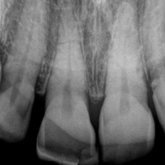

Porcelain crowns and restorations made in one appointment.

We make it a priority to incorporate the latest in dental technology in everything we do at our practice. ...